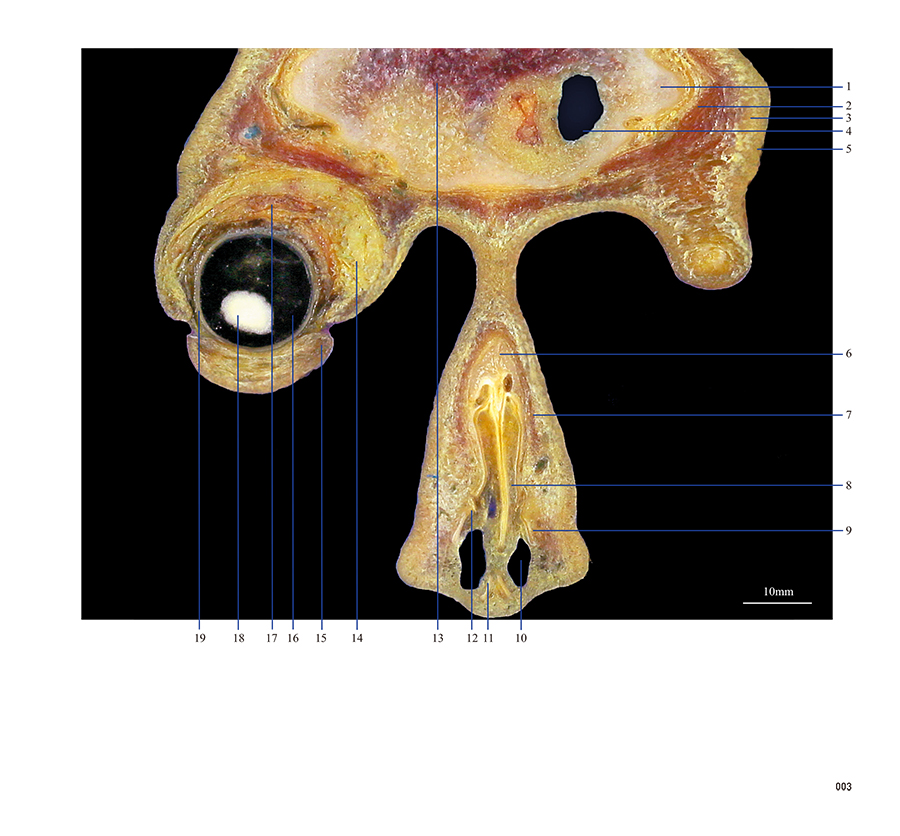

本书从数据集每隔1.2mm选取一幅图像,截取眼、耳、鼻及毗邻颅底的局部区域图像,共112幅图像。同时配以相应部位的CT图像对照。本书特色是断层解剖图利用数字图像处理技术优势,放大并清晰展示眼、耳、鼻及毗邻颅底断面的局部区域结构,组织色泽真实,甚至能够清晰显示肌肉纹理、筋膜纹路等细节结构,图像质量高于美国《人体断层解剖学彩色图谱》(引进版)类似图谱图像质量。对眼科、耳鼻咽喉科和神经内外科医生理解相关解剖结构有较大帮助。